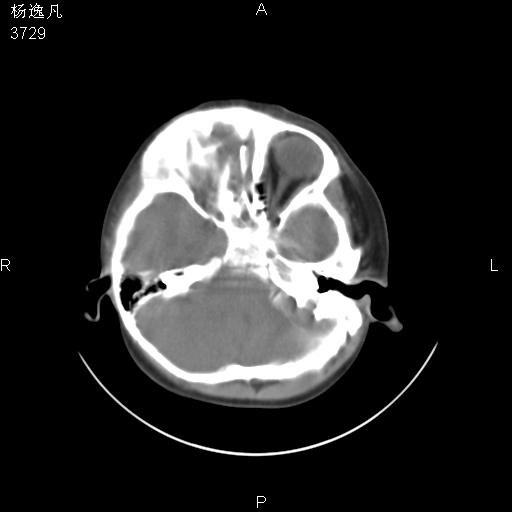

男性,5岁,面部受外伤,余无特殊

骨窗

鼻咽顶后变窄。顶后壁增厚,考虑腺样体肥大。其它未异常/

头颅ct平扫未见明确外伤性征象,右侧面部及颞部软组织肿胀,后鼻腔软组织影增大,增厚,鼻咽顶部变窄,考虑鼻咽腺样体增值肥厚。

双侧位置太不对称,未见明显骨折征象。